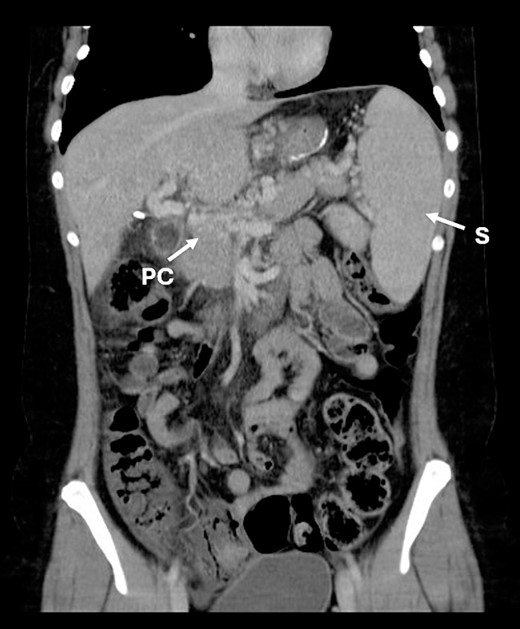

Three years after the bariatric surgery, during a routine imaging follow-up, the presence of portal cavernomatosis was detected (Fig. 1), along with significant palpable giant symptomatic splenomegaly, which subsequently led to thrombocytopenia and recurrent episodes of gingival bleeding. Furthermore, gastroesophageal varices had enlarged significantly, posing a high risk of bleeding and requiring recurrent endoscopic banding.

CT scan showing portal cavernomatosis and massive splenomegaly. PC, portal cavernomatosis; S, splenomegaly.